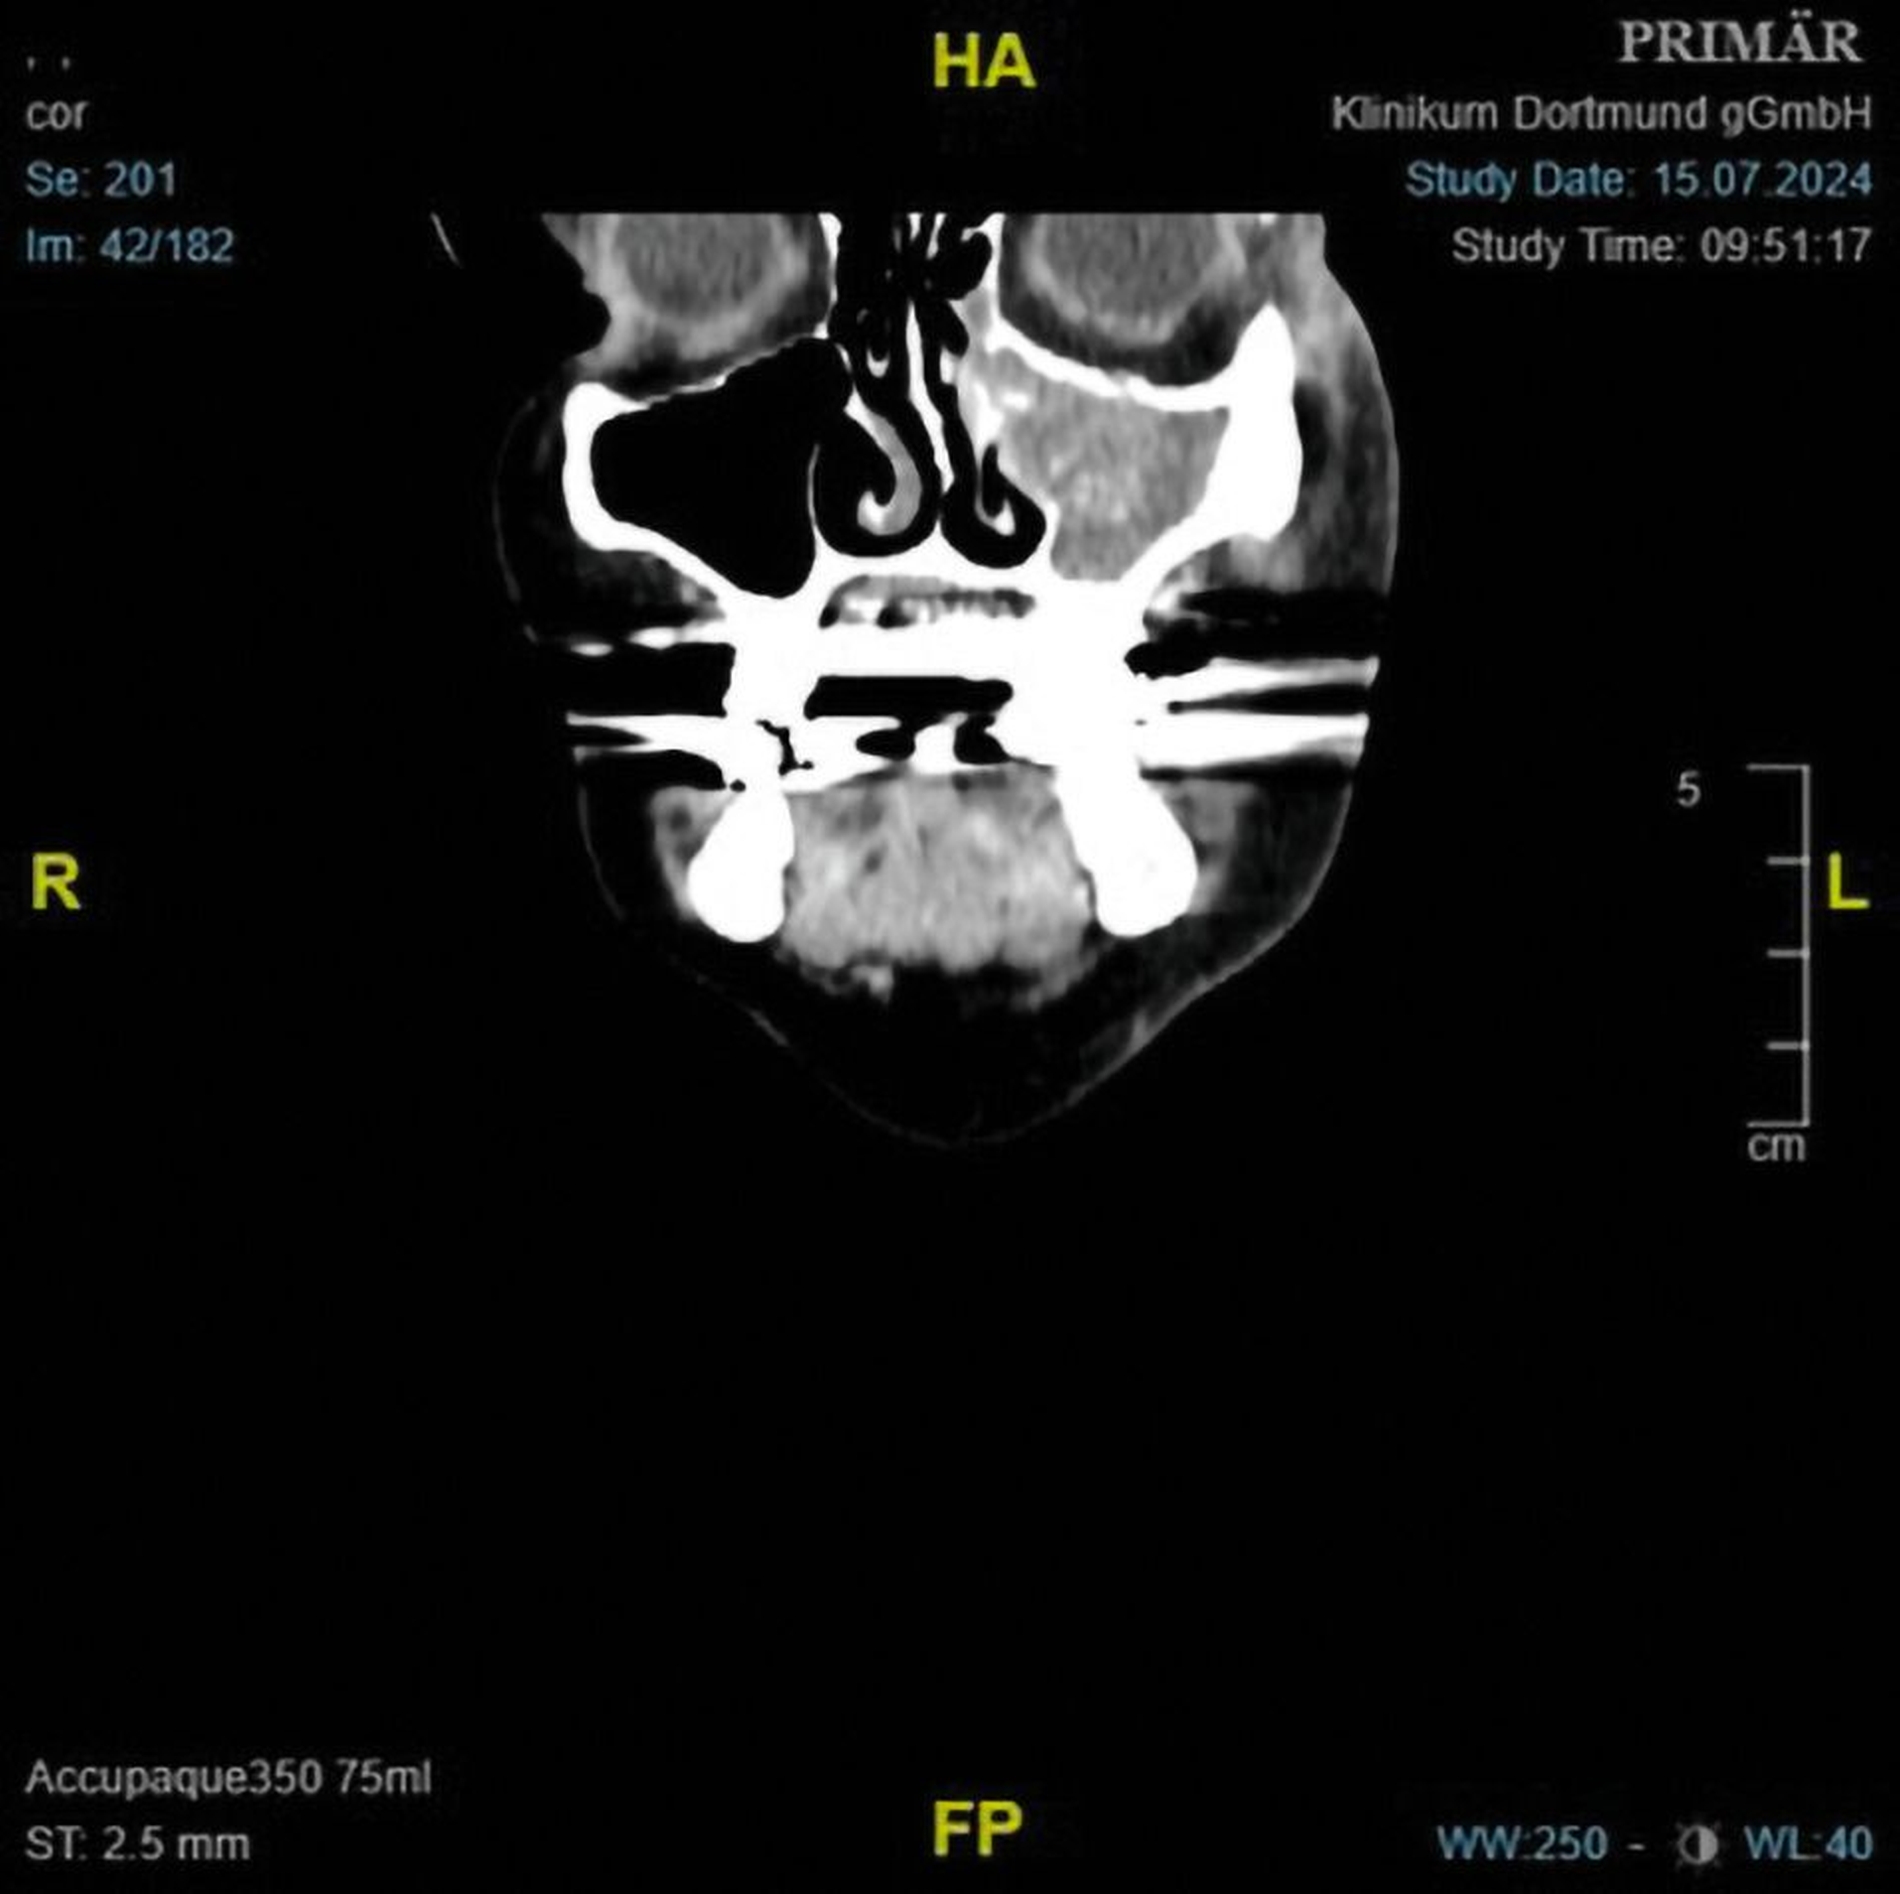

Nach ausführlicher Besprechung der Befunde und Therapiemöglichkeiten führten wir eine Exploration der linken Kieferhöhle über einen transantralen Zugang mit Fensterung des Sinus maxillaris zum unteren Nasengang sowie eine Wurzelspitzenresektion an den drei apikal beherdeten Wurzeln des Zahns 26 in Allgemeinnarkose durch. Intraoperativ konnte aus der linken Kieferhöhle reichlich schwarzes Gewebe mit Pus exkaviert werden. Ersteres war gut vereinbar mit einer Pilzinfektion. Bei der Wurzelspitzenresektion waren intraoperativ keine Pilzanteile sichtbar. In der histopathologischen Untersuchung zeigte sich ein tumorbildendes Pilzproliferat aus Mycelien mit chronisch granulozytärer Sinusitis und Osteomyelitis. Die mikrobiologische Untersuchung ergab den Nachweis von Lomentospora prolificans (Abbildung 2).

Zum Ausschluss eines disseminierten Pilzbefalls wurden in der MRT-Bildgebung vom Schädel und der computertomografischen Untersuchung vom Thorax und Abdomen sanierungsbedürftige Filiae ausgeschlossen. Die konsiliarisch durchgeführte augenärztliche Untersuchung ergab keinen Hinweis auf eine intraokulare Beteiligung. Der weitere postoperative Verlauf gestaltete sich komplikationslos mit stadiengerechter Wundheilung (Abbildung 3).